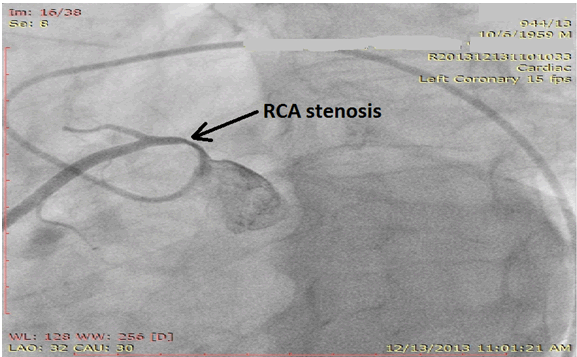

The origin and course of right coronary artery was abnormal and thus a CT angiography was performed. The CT angiography confirmed that the origin of the right coronary artery was from the left coronary sinus and that the artery coursed between the aorta and the pulmonary artery (Figure 3) and (Figure 4).

Figure 3: Computed tomography angiography. Course of right coronary artery is between Aorta and the pulmonary artery. Ao = Aorta; PA = Pulmonary artery.